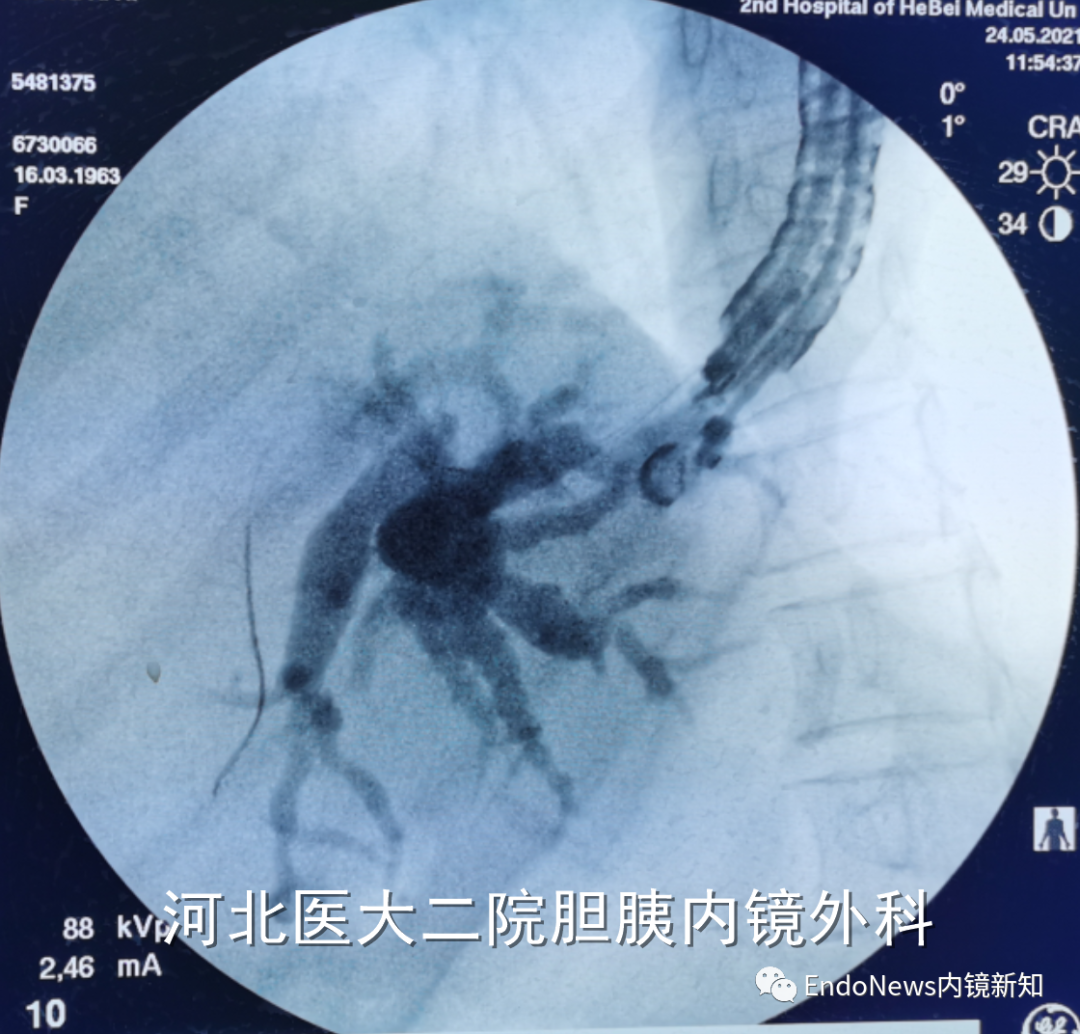

行经十二指肠胆管穿刺(CDS)时一般不需要考虑以上问题,但如因某些特殊原因涉及到会师操作时可能涉及到导丝自胆总管上游朝向下游的超选。一般情况下,CDS的时候穿刺针的方向是朝向肝内的,比如下图:

如果这个时候放支架行CDS就可以结束手术了,如果需要做顺行或者会师,就需要使导丝返折180°朝向胆管下游方向穿出十二指肠乳头。

也有一些时候穿刺后导丝方向本身就是朝向胆总管下游方向的,比如下面两个病例: